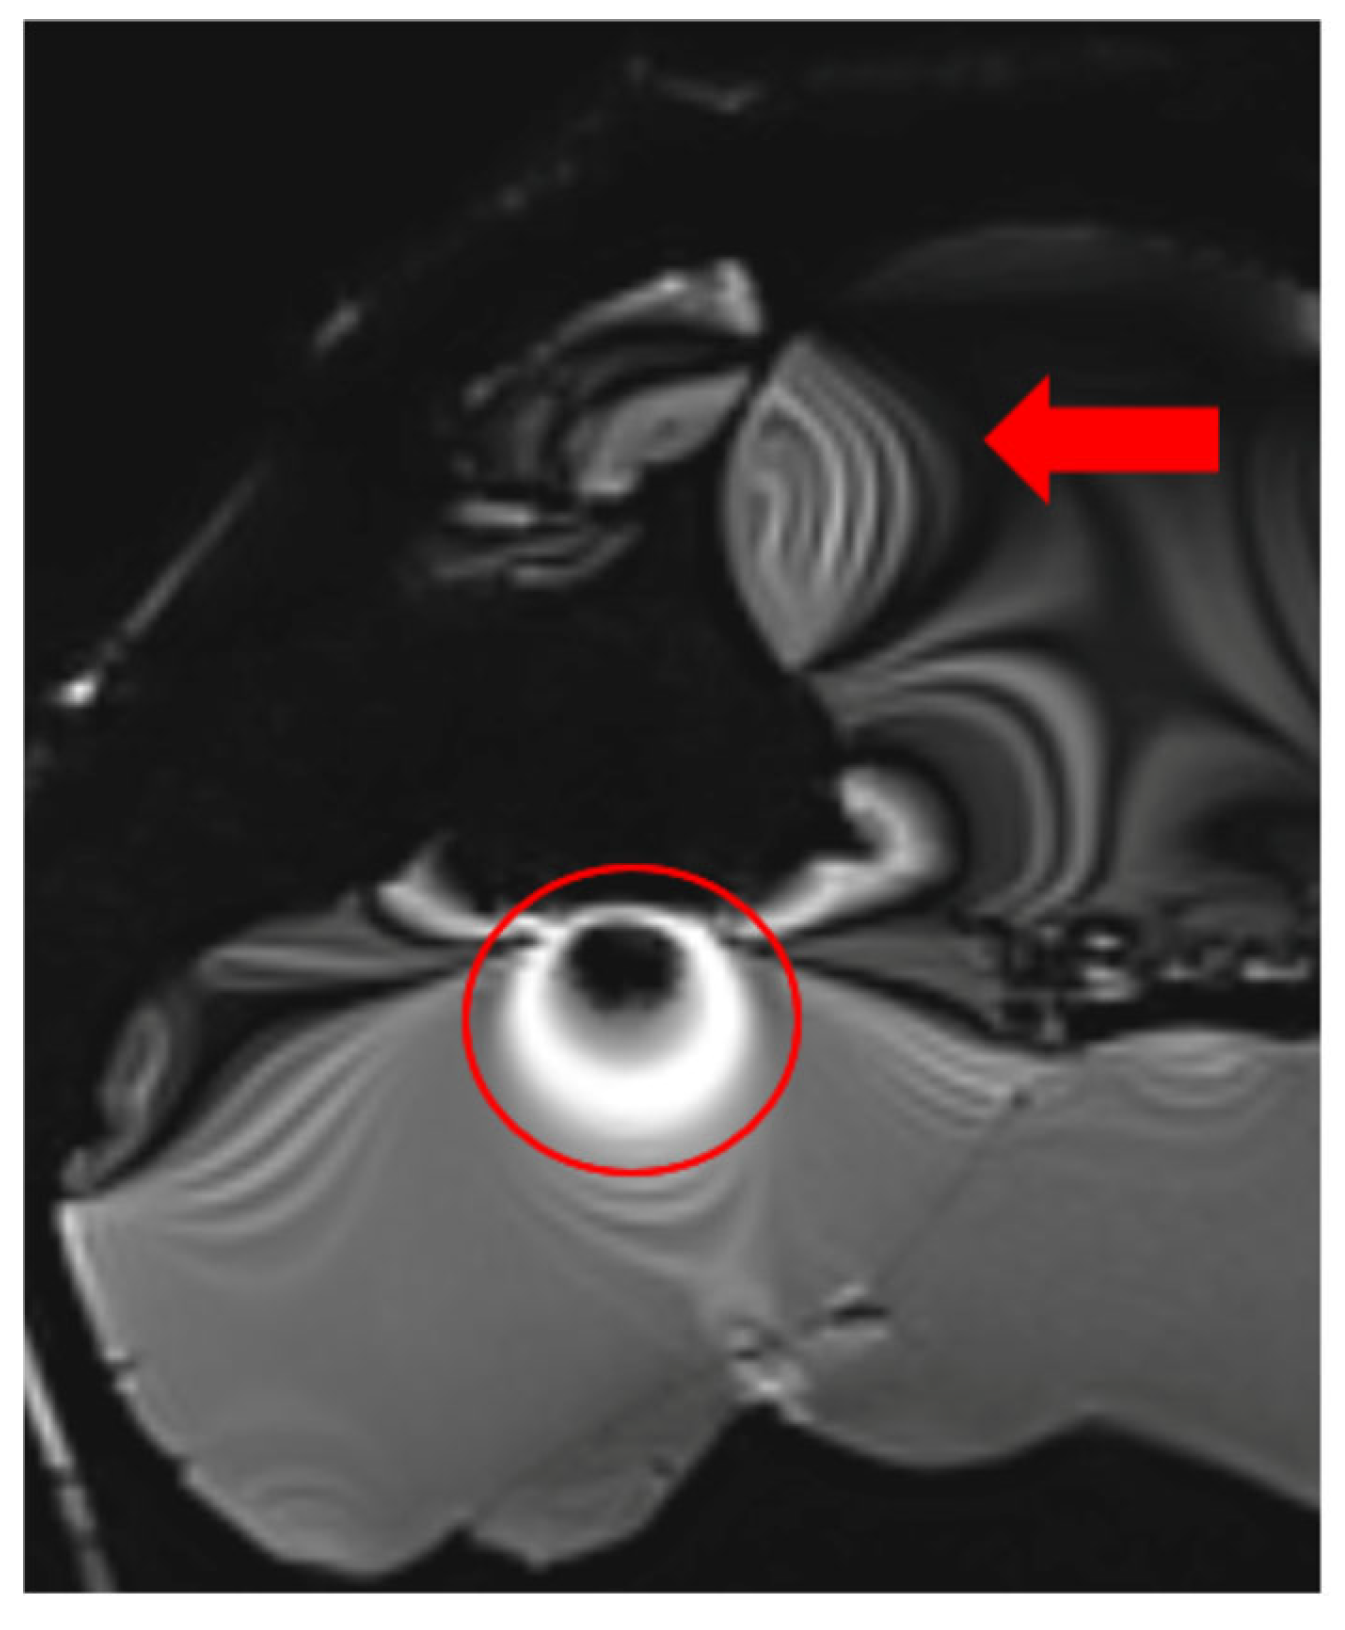

Additionally, some MRI scanners fail to adjust RF pulse voltages accurately to achieve the intended flip angles, especially when scanning smaller objects than the system anticipates. Before acquiring images, MRI scanners perform an adjustment procedure to calibrate voltage levels for standard 90° and 180° RF pulses. If the calibration is incorrect, all subsequent RF pulses will be inaccurately calculated, leading to improper image contrast. This issue is evident in the t2_space_flair_sag sequence (Figure 5).

Figure 5.

Image illustrating the effects of inaccurate RF pulse calibration on image contrast in the t2_space_flair_sag sequence, with the red circle highlighting signal amplification due to incorrect flip angle settings and the red arrow indicating spatial inhomogeneity caused by improper RF adjustment when scanning small objects.